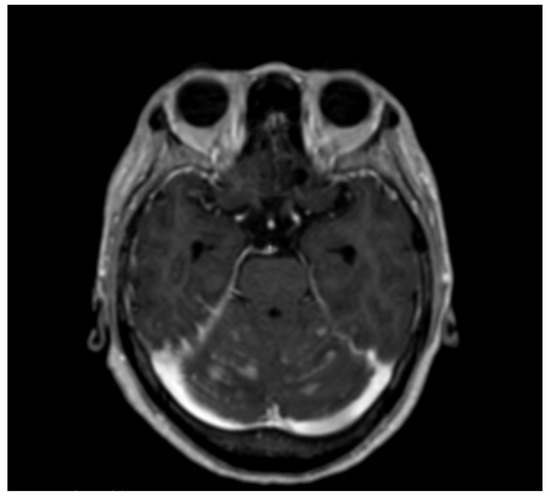

8 pages, 7998 KB

Case Report

Leptomeningeal Carcinomatosis of a Poorly Differentiated Cervical Carcinoma Caused by Human Papillomavirus Type 18

by Pierpaolo Zorzato, Mattia Zambon, Silvia Gori, Helena Frayle, Maria Teresa Gervasi and Annarosa Del Mistro

Viruses 2021, 13(2), 307; https://doi.org/10.3390/v13020307 - 16 Feb 2021

Cited by 4 | Viewed by 3682

Abstract

Cervical cancer is caused by a persistent infection with high-risk types of Papillomaviruses (hrHPV); HPV16 and HPV18 are associated with about 70% of the cases. In the last decades the introduction of a cervical cancer screening has allowed a decrease in cervical cancer [...] Read more.

Cervical cancer is caused by a persistent infection with high-risk types of Papillomaviruses (hrHPV); HPV16 and HPV18 are associated with about 70% of the cases. In the last decades the introduction of a cervical cancer screening has allowed a decrease in cervical cancer incidence and mortality; regular adhesion to the screening procedures, by pap test or HPV test, and colposcopy, according to the international guidelines, prevents cancer development and allows for diagnosis at the early stages. Nowadays, in industrialized countries, it is not common to diagnose this pathology in advanced stages, and this occurrence is frequently associated with patient’s unattendance of cervical screening programs. We describe a case of delayed diagnosis of cervical cancer, posed only after the onset of the neurological symptoms caused by leptomeningeal metastases, despite a two-year history of abnormal cytology. The endocervical mass was analyzed by immunohistochemistry, and search and typing of HPV sequences was performed by PCR in the meningeal carcinomatous cells. A poorly differentiated squamous cell carcinoma was diagnosed, and HPV18 sequences were detected. This rapidly fatal case highlights the importance of following the evidence-based recommended protocols and the preventive role of the population-based cervical cancer screening programs. Full article

(This article belongs to the Special Issue HPV and HPV Vaccine)

Show Figures

Figure 1